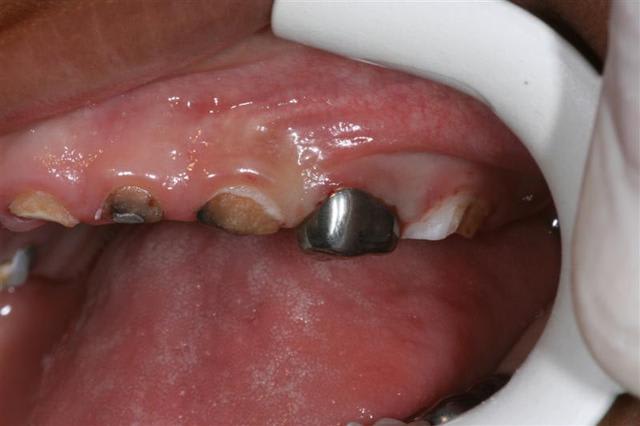

ds la mme,je récupère le frère

kelly:3 ans et 4 mois

Img 0965  small  ew2zyp - Eugenol

Img 0967  small  dahzlx - Eugenol

Enfin, comme on dit mieux vaut tard que jamais!! J'ai vu un petit comme ça en vac de pédo au centre de soins, 3 ans et demi, le père a laissé tomber au bout de 2 séances... C'est tellement égoïste je trouve de la part des parents de laisser leur gamin comme ça! Ceci dit je suppose que comme ça s'est bien passé avec antoine, ils vont faire la totalité des soins avec le petit, c'est déjà ça :)

Bon, vu la photo, je suppose que t'as des extractions et une petite prtohèse amovible prévues?

pr sig,les extractions st faites,les soins aussi,une couronne pedo est prévue en fevrier et la prothèse amovible pas faite: je n'ai pas de prothesiste pedo sur place et je ne suis pas persuadée qu'il va la porter